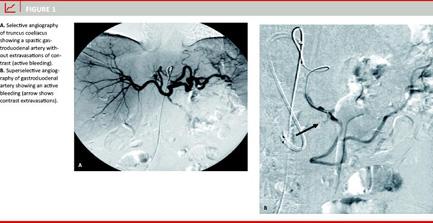

A total of 40 patients underwent embolisation procedures with 100% primary technical success. The patient population comprised 26 men and 14 women. The mean age was 67.4 years (range: 31-92 years). The bleeding causes were duodenal ulcer in 21 patients (52%), gastric ulcer in eight patients (20%), complicated pancreatitis in seven patients (18%) and pancreatic carcinoma in four patients (10%). Comorbid conditions were respiratory in eight patients (28%), cardiovascular in five patients (17%), malignant diseases in two patients (7%), renal failure in three patients (10%), coagulopathy in eight patients (28%) and multiorgan failure in three patients (10%). The gastroduodenal artery was embolised in 36 cases (90%) with coils. In nine cases angiography of the superior mesenteric artery also revealed back-bleeding from the inferior pancreatico-duodenal artery which was also embolised to achieve complete angiographic haemostasis. In one patient, embolisation of the gastroduodenal artery was performed from the superior mesenteric artery because the coeliac trunk had a severe stenosis. In another case, additional microparticles were injected to achieve complete haemostasis. The left gastric artery was embolised in two cases (5%). The splenic artery was embolised in two cases (5%). In all patients angiographic cessation of the bleeding was achieved. In 23 patients (57%), "blind" embolisation was performed. In 15 patients (38%), it was possible to visualize the bleeding artery by angiography (extravasation of contrast) (Figure 1, and Figure 2). In two pati-ents (5%), pseudoaneurysms of the gastroduodenal artery were found. There were two cases (5%) of clinically insignificant inadvertent dislocation of coils distally into hepatic and splenic arteries. No other complications were related to the intervention. Clinical success was achieved in 33 patients (82%). Seven patients (18%) had early re-bleeding within 4.2 days (range: 1-11 days). A second transcatheter embolisation was performed in three of these patients with clinical success. In the remaining four patients, haemostasis was not achieved. The repeat angiographies revealed that previously embolised arteries were non-bleeding, but other vessels were the causes of rebleeding. Thirty-three patients (82%) were discharged after clinical recovery without further surgical or interventional therapy. Four patients (10%) died during hospital stay due to continuous GI bleeding. The mean follow-up period was 13 months (range: 1-31 months). At follow-up there was no clinical suspicion of GI ischaemia in any of the patients. In the group with clinical success, five patients died (15%) from non-bleeding related diseases: prostate carcinoma (n = 1) cholangiocarcinoma (n = 1), cardiac failure (n = 2) and hepatic failure (n = 1) in the follow-up period.